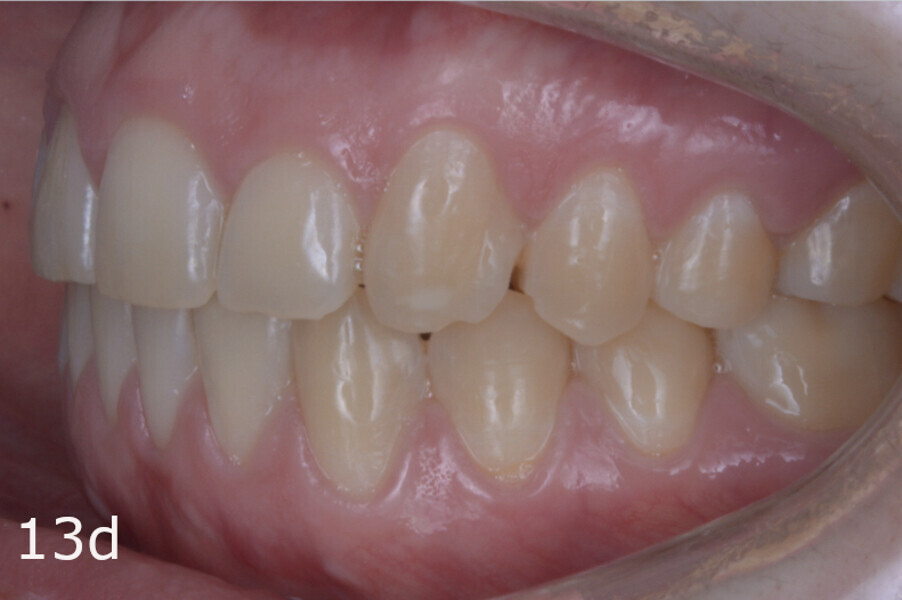

The total treatment time was 15 months. An Angle Class I relationship was established along with adequate anterior and canine guidance, establishing a functional occlusion. This not only ensures optimal masticatory function but also protects the teeth and the temporomandibular joint from excessive force. Maxillary and mandibular fixed retention were installed at the end of the treatment (Figs. 13–19).